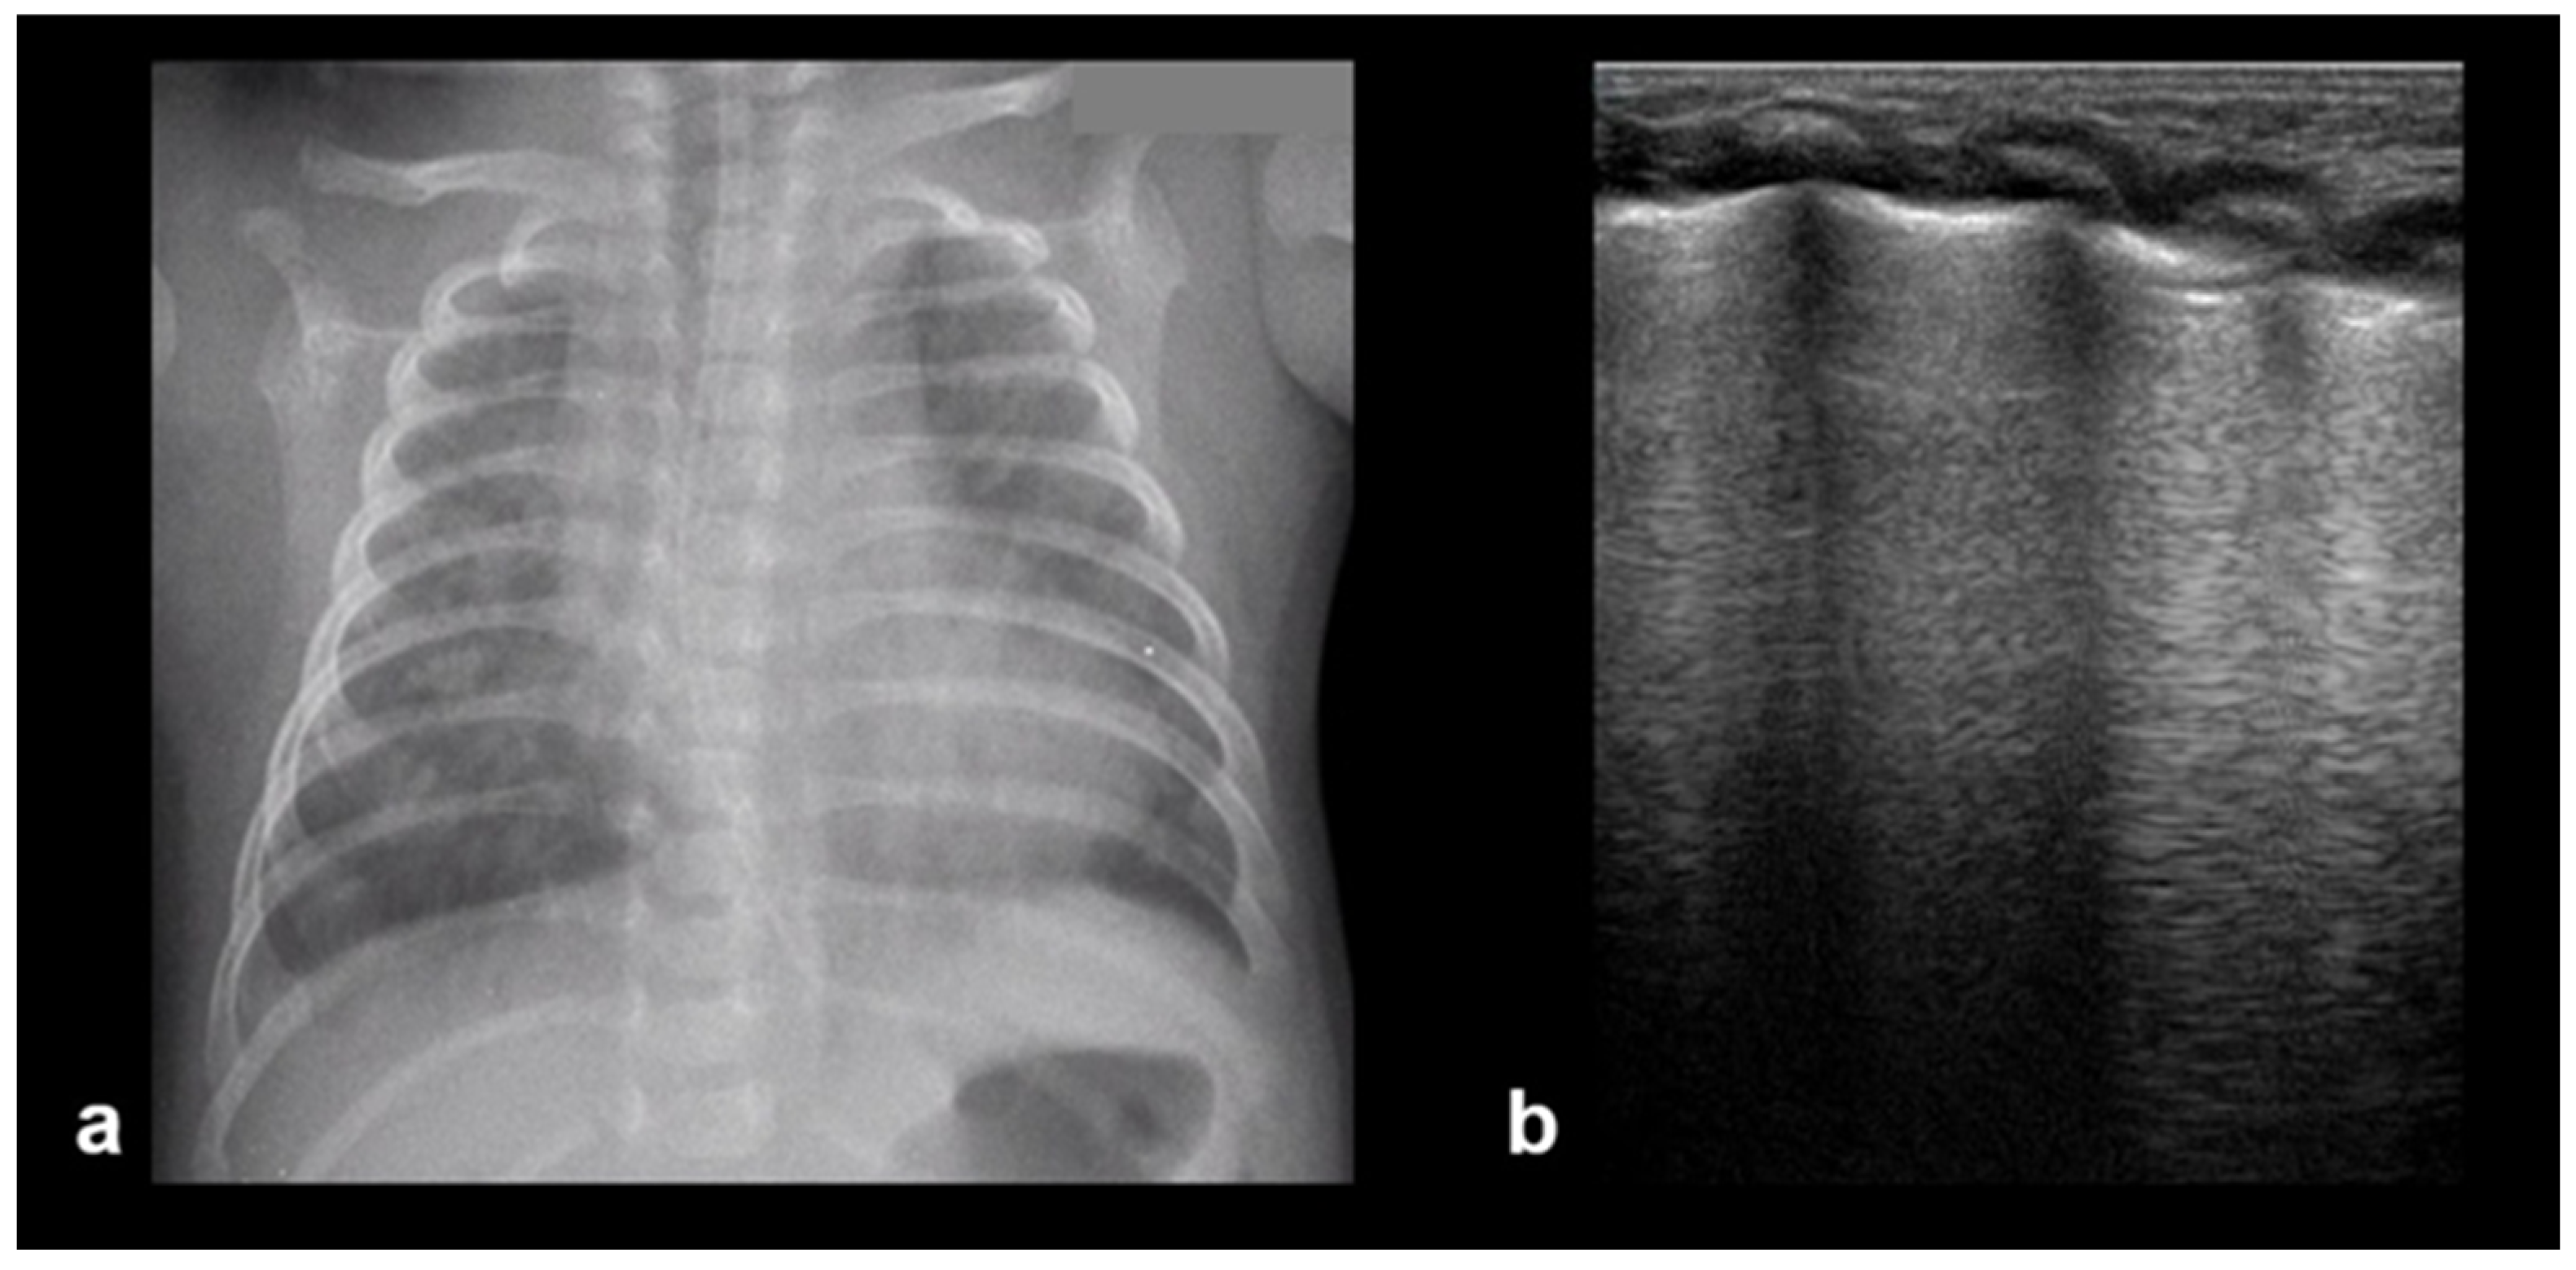

3.1.6. Sinusoid Sign

In cases of pleural effusion, the accumulation of fluid between the pleural layers causes separation of the visceral and parietal pleura. LUS assessment of this condition in M-mode is associated with the presence of a characteristic sinusoidal pattern, resulting from the cyclical movement of the lung line toward the pleural line during inhalation and away from the pleural line during exhalation. The presence of this “sinusoid sign” indicates the presence of low-viscosity fluid within the pleural space, separating the visceral and parietal pleura. This finding can assist in differentiating pleural effusion from pleural thickening, as its presence is indicative of mobile, free-flowing fluid typically associated with pleural effusions (Figure 7) [17].

Figure 7.

Sinusoid sign: (a) CXR: left-sided consolidation (is there any pleural effusion?). (b) LUS reveals fluid, a finding based on the sinusoid sign, with a characteristic sinusoidal pattern due to the cyclical movement of the lung line toward the pleural line during inhalation and away from the pleural line during exhalation (L: lung; SPL: spleen).